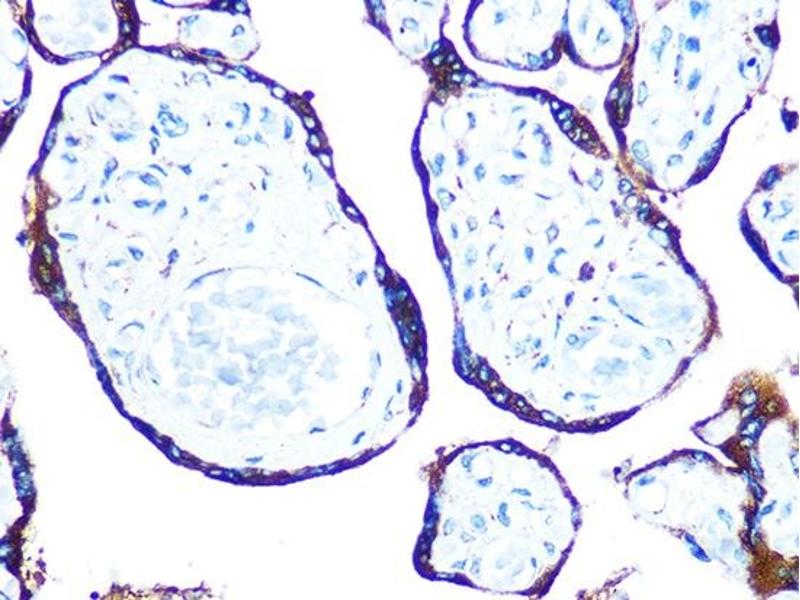

- WB,1:500 - 1:2000,IHC,1:50 - 1:200